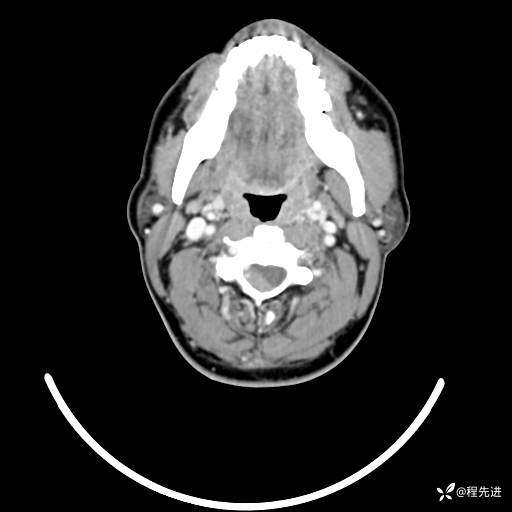

CT平扫+增强: